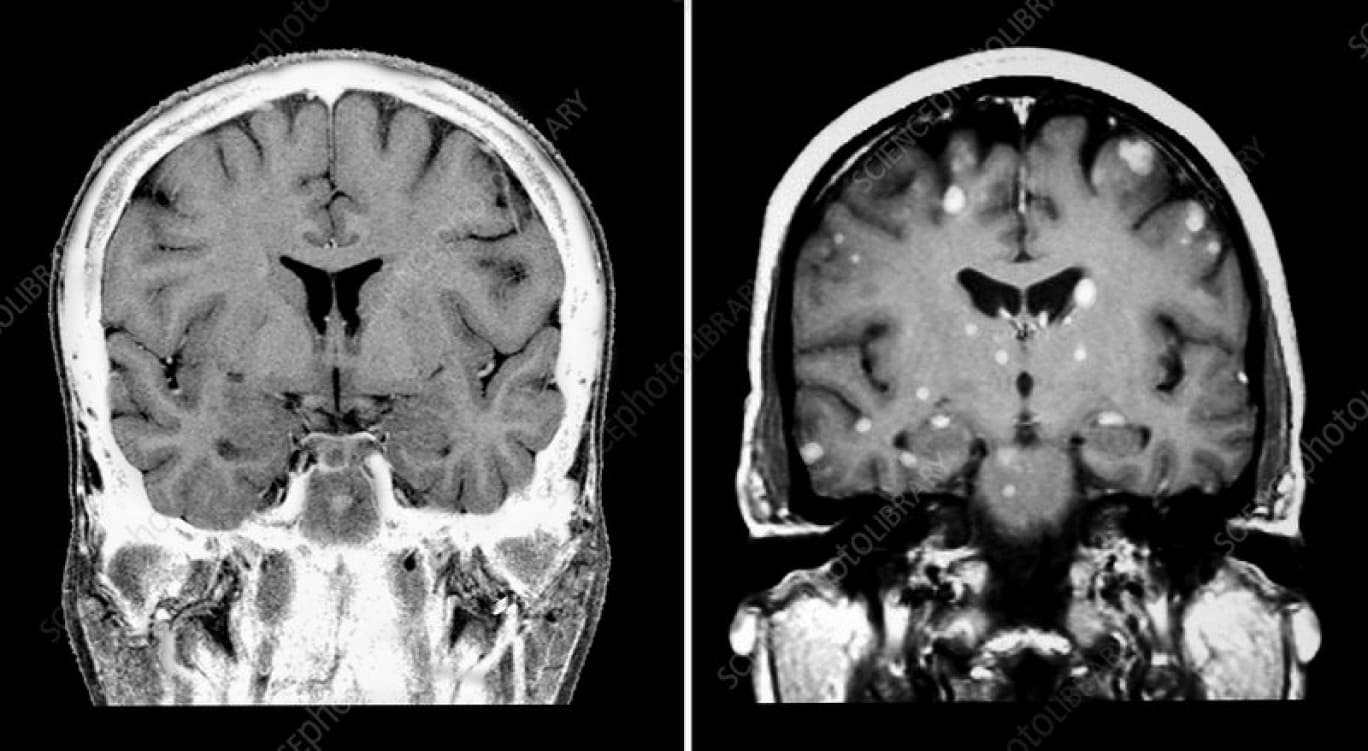

Вы решаете провести магнитно-резонансную томографию головного мозга с внутривенным контрастированием. И обнаруживаете, что объем поражения головного мозга несколько больше, чем представлялся ранее. Выявлено еще несколько очагов в обеих долях головного мозга.

Рис. 2 — срезы выполненной магнитно-резонансной томографии головного мозга с внутривенным контрастированием. Отмечается двустороннее поражение больших полушарий. С учетом анамнеза, очаги, наиболее вероятно, вторичного (метастатического) генеза.